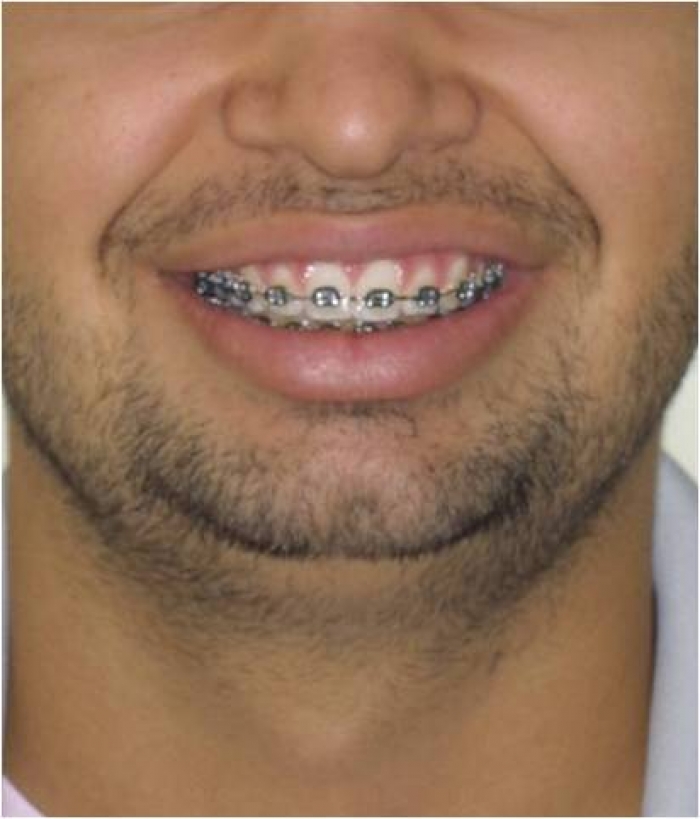

Sorriso inicial

Sorriso após cirurgia